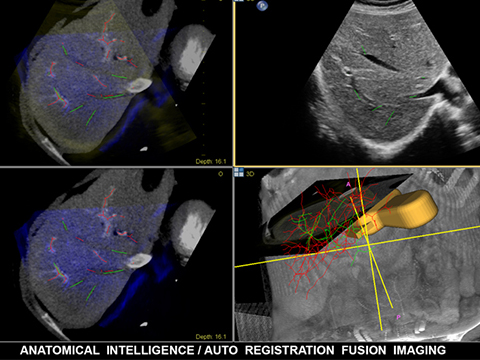

Anatomical Intelligenceは、EPIQ、Affiniti、EchoNavigatorなどをはじめとするフィリップスのイメージングソリューションで使用されています。解剖学的構造の異常などを迅速かつ確実に特定し、治療法の決定やインターベンション時のガイドに役立っています。

EPIQ CVxiはインターベンションエコーガイダンスの新しい方向性を示す製品です。要求の高い今日の医療課題を克服するため、多様な患者およびインターベンション手技に対応する高いレベルの臨床性能を備えています。装置上から直接、新しいEchoNavigator R3を操作することができ、ライブフュージョンイメージングの新しい合理化されたワークフローを実現します。